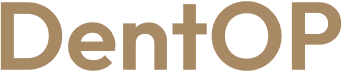

Situația inițială a fost dezastruoasă, dar am reușit să-i redăm zâmbetul cu ajutorul implanturilor dentare

Se simte foarte bine după cele 6 luni, este mulțumită și fericită că poate zâmbi din nou, iar asta se observă și pe chipul său.